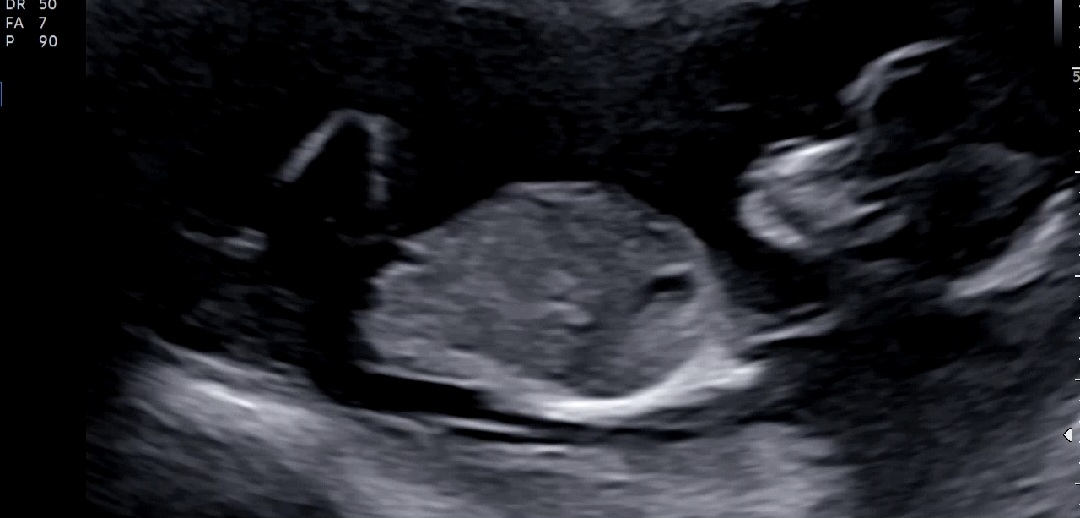

확실하진 않겠지만 13주 각도 어때용ㅜㅜ?

정확하진 않겠지만 어때보이세용?-? 곧 알게 되겠지만 넘 궁금해욧😆😆😆